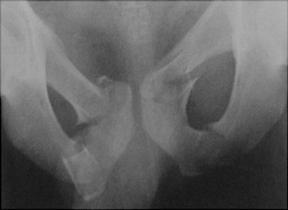

Cistograma Fracturi ale ambelor

ramuri pubiene

Contur neregulat al vezicii urinare Disjunctie

sacro-iliaca dreapta

Hematom pelvian

Disjunctie de simfiza pubiana Disjunctie

de simfiza pubiana